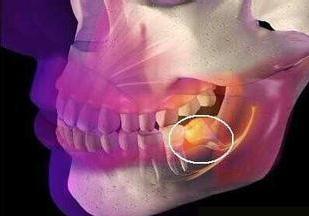

当智齿的牙齿没有足够的空间通过牙龈喷发时,就会发生冠周炎。 结果,它们可能仅部分通过牙龈,这可能导致发炎和智齿周围的软组织感染。

牙医经常在临床评估过程中诊断冠周炎。 牙医将通过检查智齿并检查体征和冠周炎的外观来诊断病情。

牙医还可能需要进行X射线检查,以检查智齿的排列并排除引起疼痛的其他可能原因,例如蛀牙。